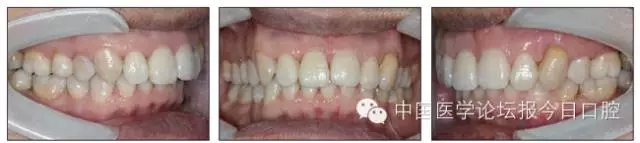

口內情況:恒牙列,24、34、44缺失,磨牙Ⅲ類關系,上牙列散隙,上前牙扇形漂移。前牙深覆(牙合)、深覆蓋。口腔衛(wèi)生較差,11與12間牙齦乳頭紅腫,多個牙探診有牙周袋形成,11松動Ⅰ度,余切牙松動(-),患者面像及口內像如圖1、2所示。

4.webp.jpg

圖2 治療前口內像